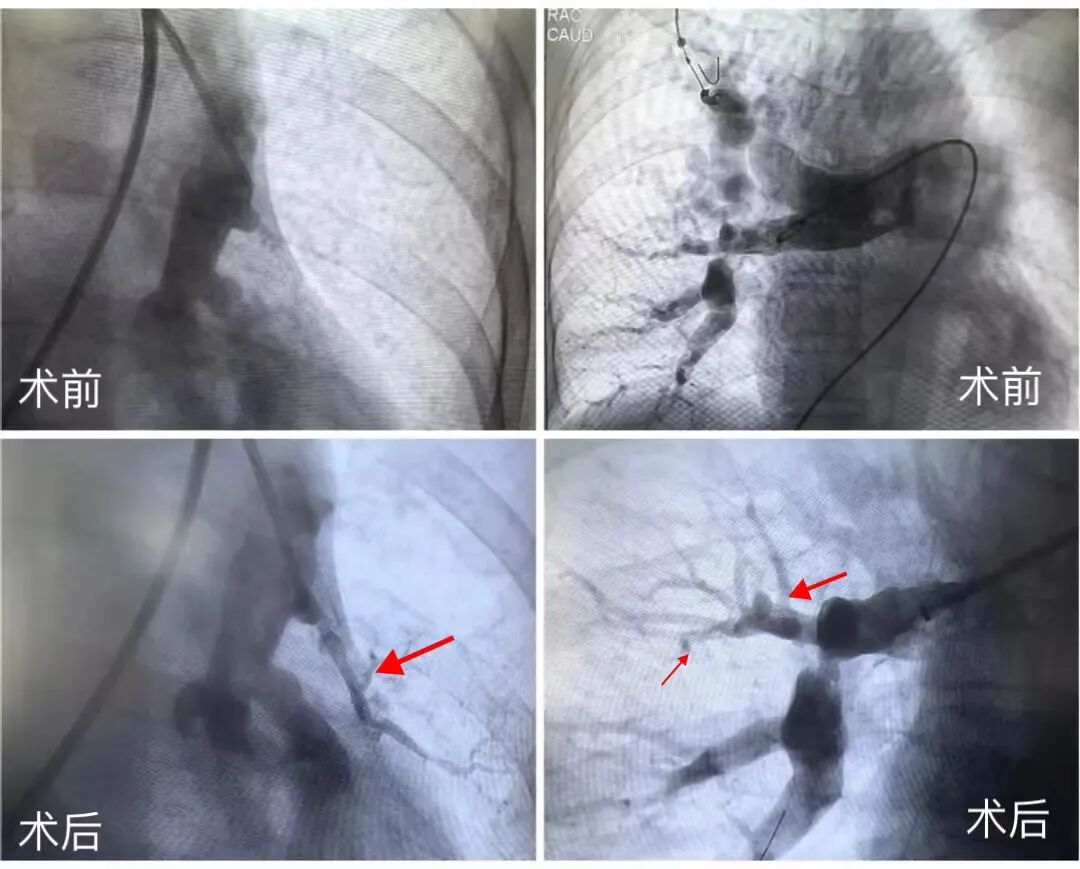

3月29日,内蒙古自治区人民医院呼吸与危重症医学科联合多学科团队,成功独立完成一例复杂经皮肺动脉球囊扩张成形术。此次手术的独立成功实施,充分展现了内蒙古自治区人民医院呼吸与危重症医学科呼吸介入团队(肺血管方向)处理复杂病例的高超医疗水平及丰富的临床经验。

患者为老年女性,反复发作胸闷、气促30余年,活动后明显,长期未重视,近期上述症状明显加重。肺动脉CT造影检查提示提示多发肺动脉狭窄、闭塞。

经综合分析,该患者被诊断为慢性肺血栓栓塞性肺动脉高压。呼吸与危重症医学科主任徐毛冶教授组织开展由呼吸与危重症医学科、介入医学科、影像医学科、药学处及护理团队组成的院内肺血管MDT,经过系统评估病情后,讨论后决定采用微创介入治疗方法——经皮肺动脉球囊扩张成形术,逐步解除困扰患者多年的肺动脉闭塞及狭窄。

本例患者的微创治疗是由区内呼吸介入团队(肺血管方向)独立完成的手术。经过徐毛冶教授及呼吸介入学组的扩大讨论,由呼吸与危重症医学科苏鲁德夫副主任医师与介入科石宝琪教授团队张伟副主任医师共同实施介入治疗手术。手术团队顺利扩张了狭窄的右下肺动脉,开通了闭塞的右肺A9A10,A1A3分支共5支血管,手术时长2小时。患者术后病情得到极大改善,血氧饱和度上升,呼吸困难症状明显缓解,活动耐量明显增加。